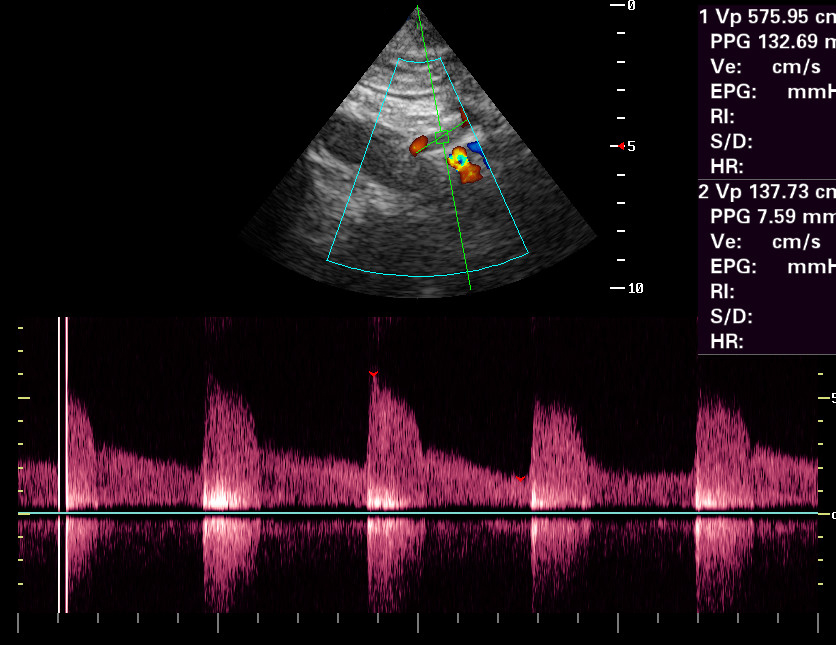

Стеноз tr caliacus: доплер

Женщина 66 лет.

Жалобы на постоянные боли в эпигастральной области.

УЗИ ОБП - атеросклеротические изменения аорты.

Заказ хирурга - исключить стеноз tr caliacus.

Доплерограмма - ниже

oct292014105125_8.jpg

Есть или нет?